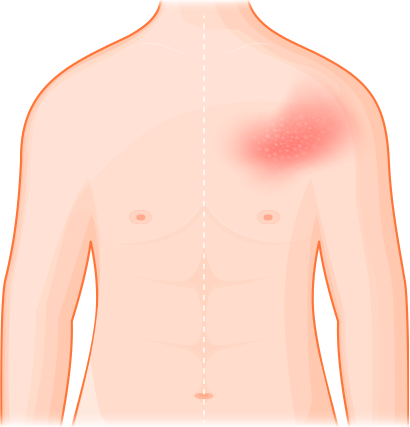

대상포진 주요 증상

피부에 물집이 나타나기 전에 대상포진이 나타나는

신경절을 따라 통증과 이상감각이 생길 수 있습니다. 경우에 따라 심한 통증과

가려움증이 동반되는 경우도 있습니다.

보통 신체의 한쪽으로 볼록 튀어나온 홍반성 구진 형태로

시작되어 물집으로 바뀌게 됩니다. 물집은 시간이 지나면서 딱지로

생기면서 호전되기 시작합니다.